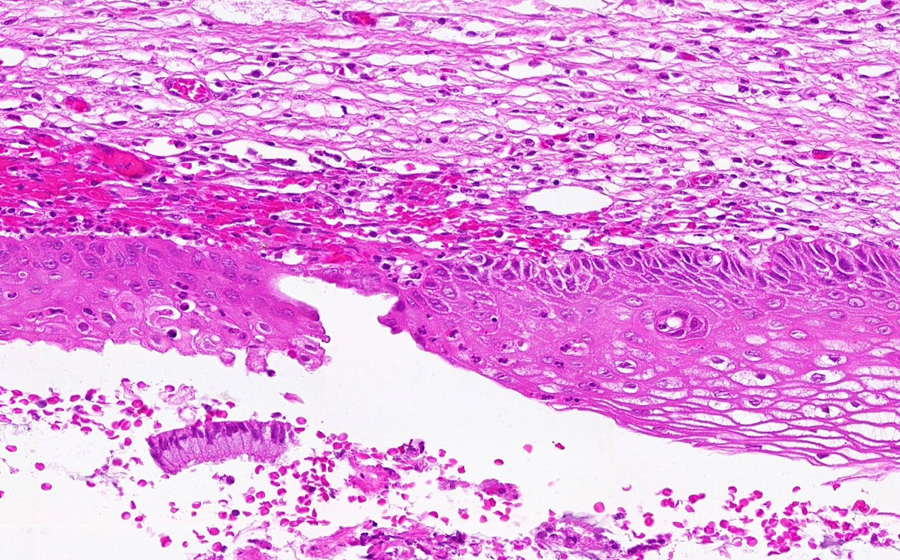

Slide 3: Chronic cervicitis and metaplasia

Histologic section of cervix from a patient with chronic cervicitis (click here to review normal tissue)

Image 2 - 50X

Slide 3 - Image 2